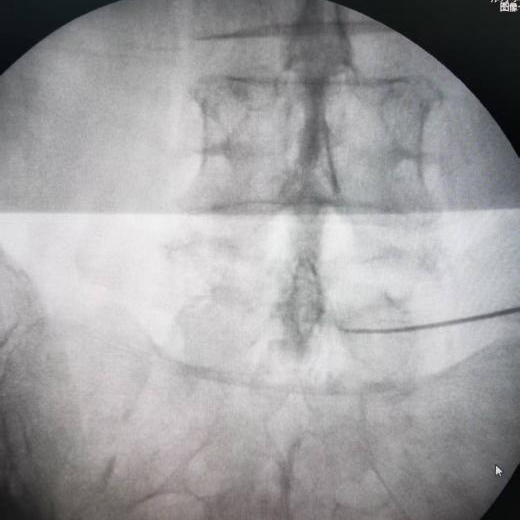

(一)C臂或CT引导下椎间盘微创消融术

通过射频针穿刺至突出椎间盘内,利用针尖发热使周围髓核凝固皱缩,从而缩小椎间盘体积,减轻神经压迫。